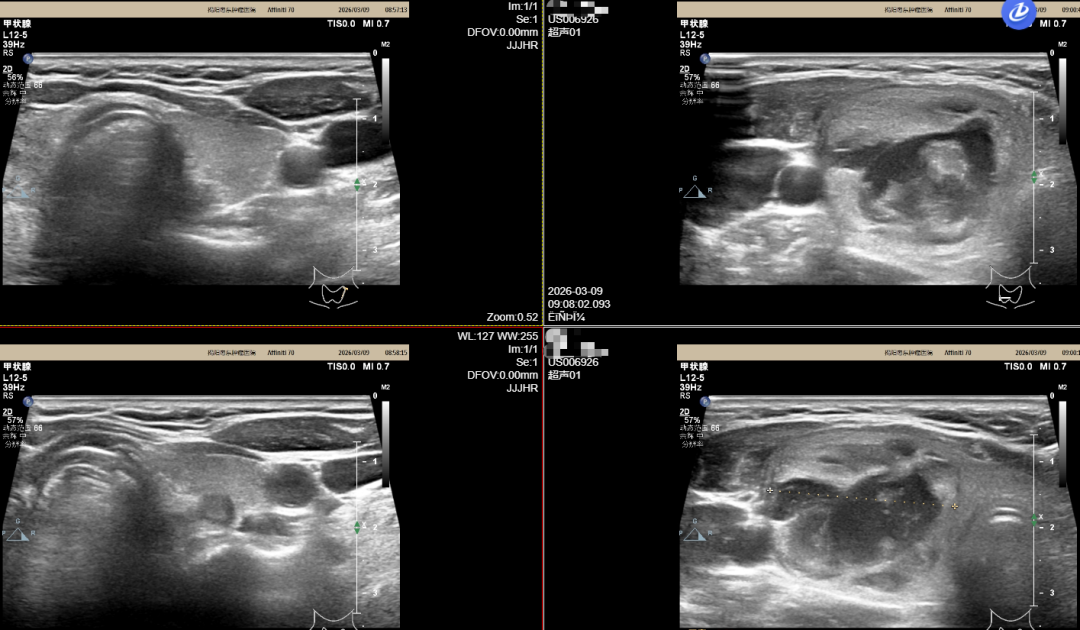

案例二

患者为54岁女性,因“发现右侧甲状腺肿块1年余”入院。该名患者于1年前发现右侧甲状腺肿块,大小约50px × 75px,无声音嘶哑、饮水呛咳等不适,肿块未见明显增大,2026年2月外院甲状腺彩超提示双侧甲状腺结节。

影像学报告提示该名患者甲状腺右侧叶可见一大小约38mm × 28mm × 27mm的囊实混合性结节,左侧叶中部近后被膜见一大小约6mm × 5mm的实性结节。最终在我院接受了甲状腺结节微波消融术,术后恢复良好,颈部仅可见微小针孔,术后第二日即可出院。